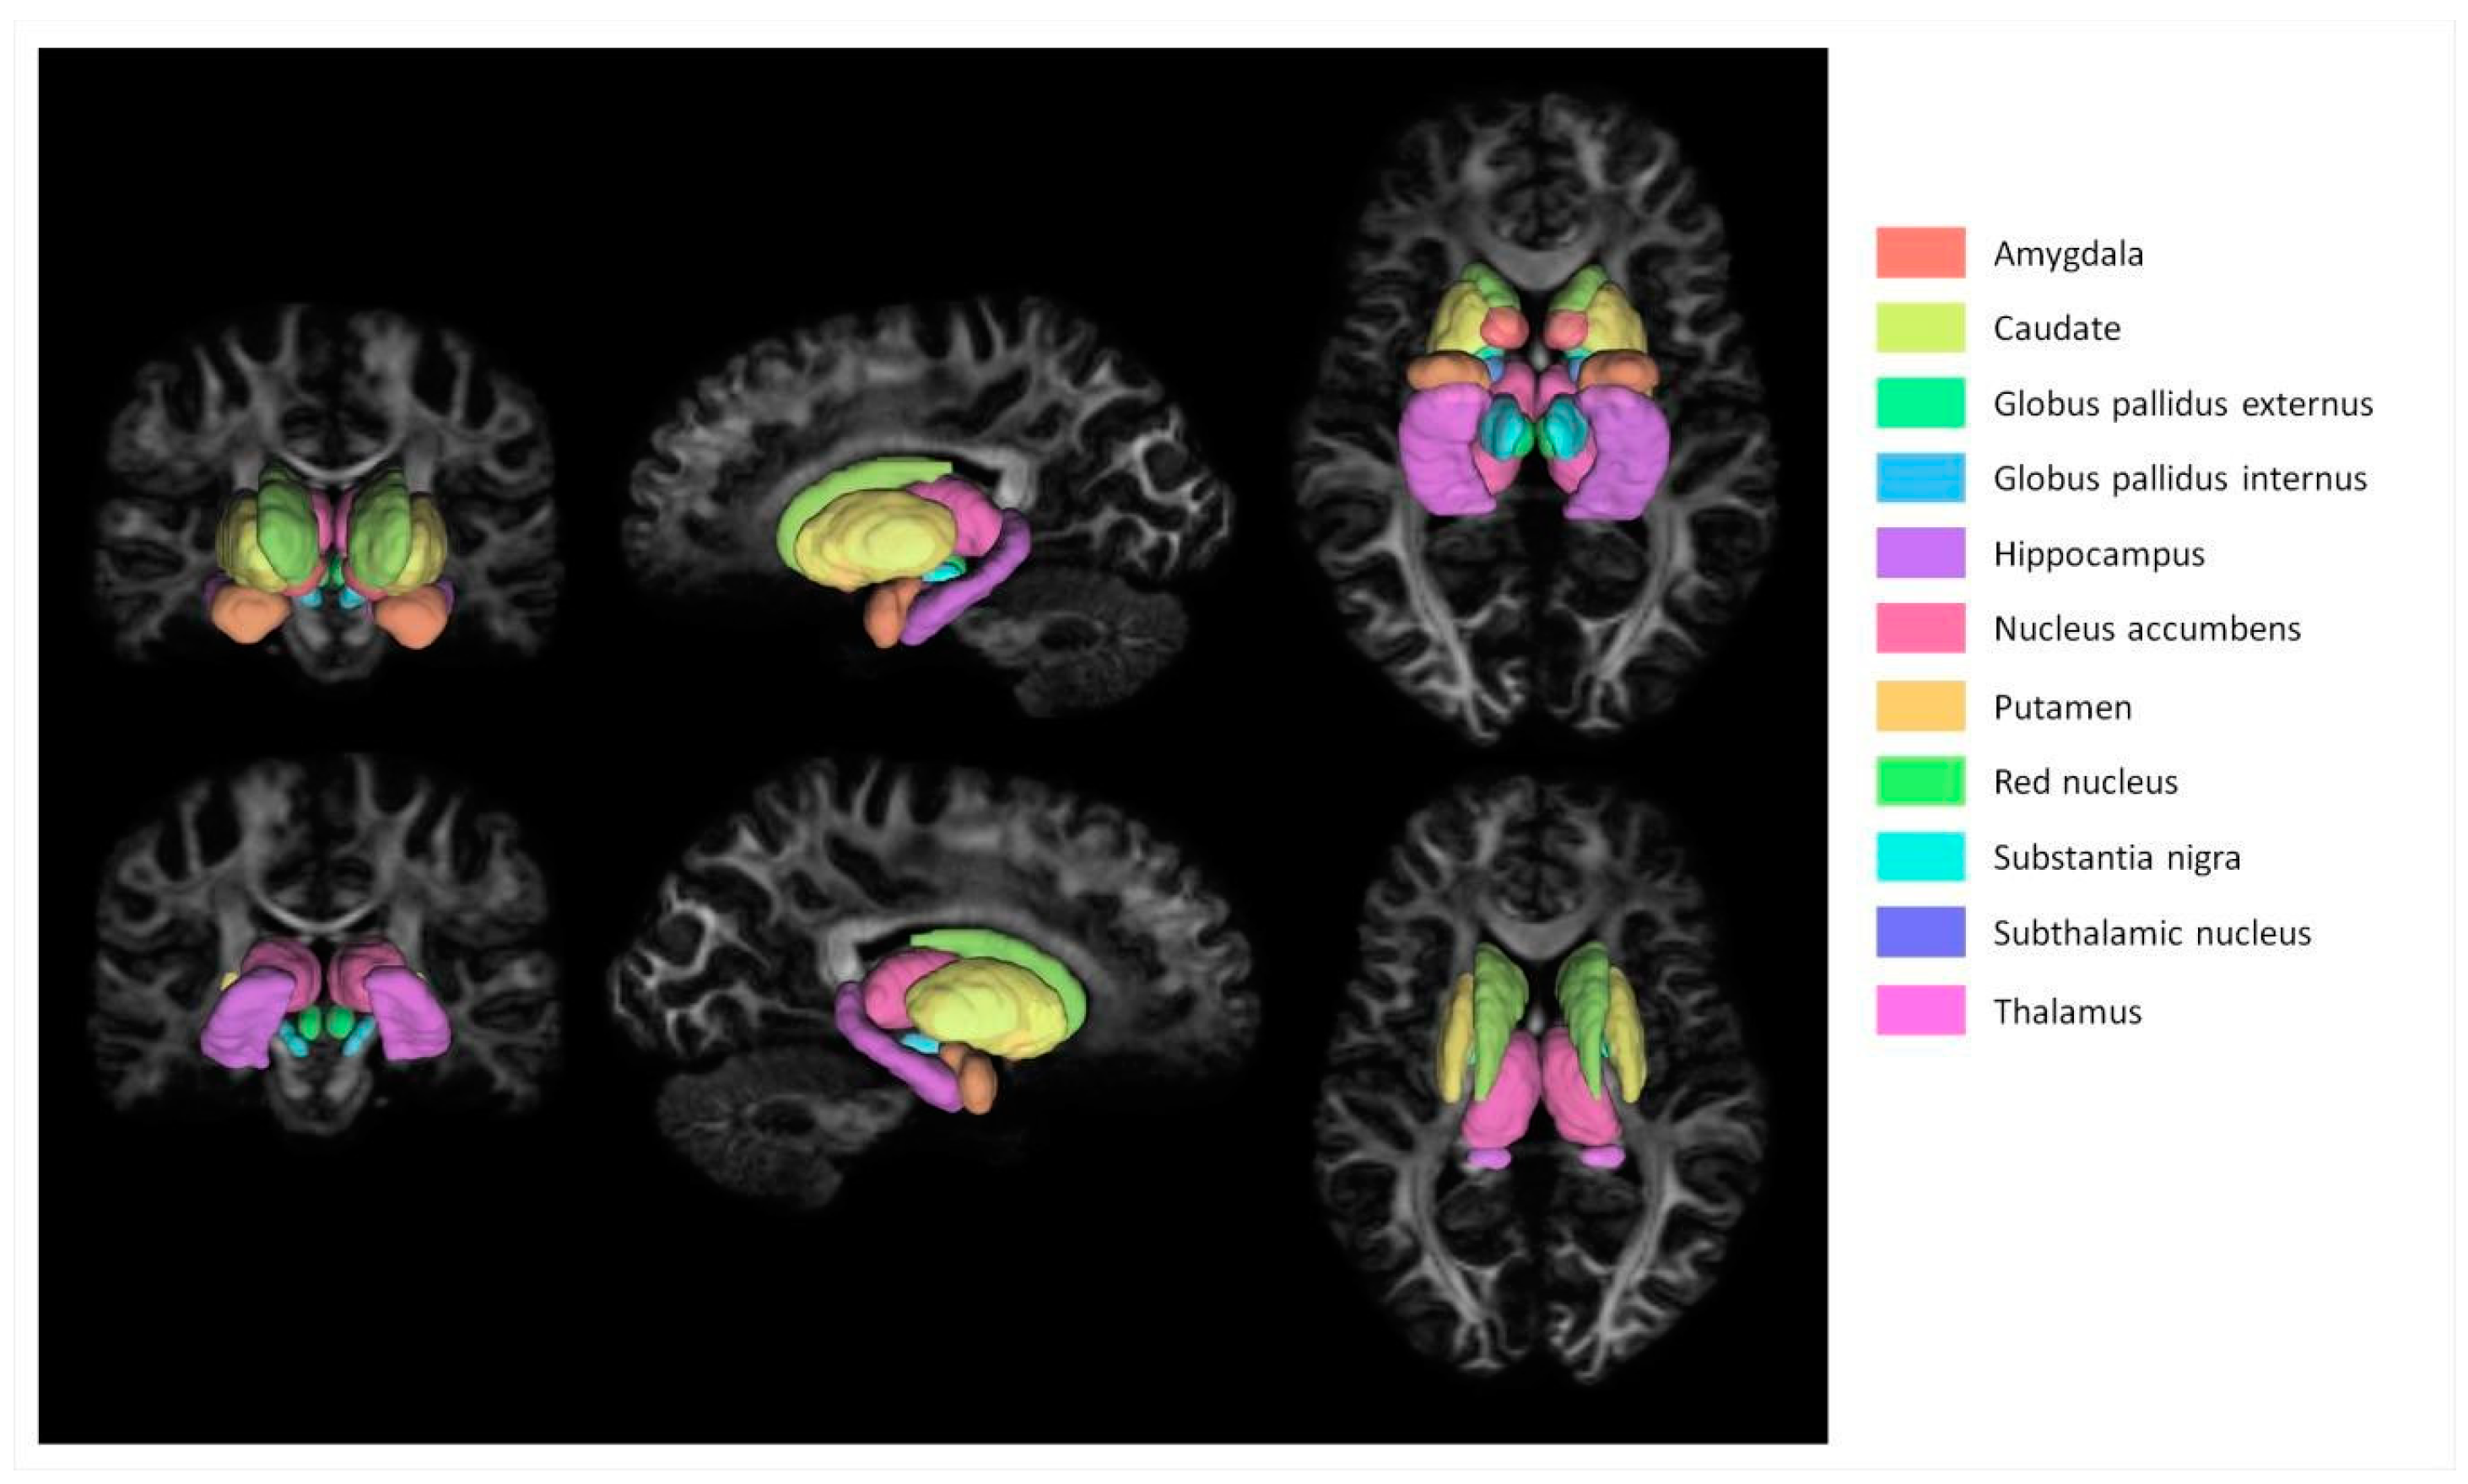

2.3. Image Processing

2.4. Diffusion Processing